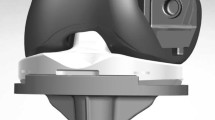

The KneeSIM program uses the Parasolid geometry of the femoral and tibial components, as well as tibial and patellar inserts for analysis. Parasolid models of a fixed-bearing flat design PS TKA (NexGen LPS-Flex; Zimmer, Warsaw, USA), including a patellar component, were imported into the program.

In aligning the components in the coronal plane, the femoral component was set perpendicular to the mechanical axis that connected the centre of the knee and the centre of the femoral head, and the tibial component was set perpendicular to the mechanical axis that connected the centre of the knee and the centre of the ankle joint. For the sagittal alignment, the femoral component was aligned to the distal anatomical axis of the femur, and the tibial component was aligned to the proximal anatomical axis of the tibia with a 7° posterior slope. The neutral rotational alignments of the femoral and tibial components were positioned in line with the femoral epicondylar axis and the tibial anteroposterior axis, respectively.